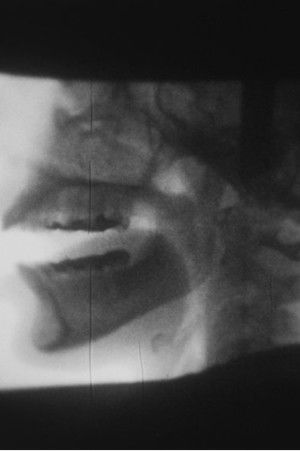

X-ray(1975)

In X-Ray, Ana Mendieta uses a Cinefluorography unit, a medical tool usually employed for diagnostic and research procedures. In Mendieta’s hands, she takes us inside her own head, filming her own X-Rayed skull while talking.